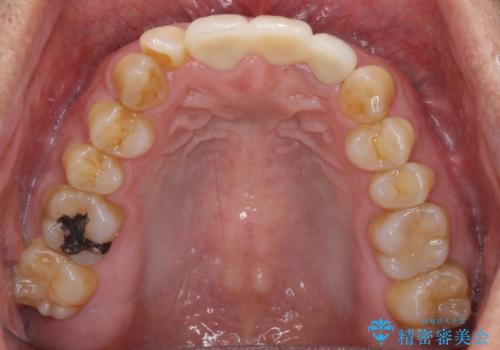

神経の抜かれている土台の歯は根管治療を行った上で、オールセラミックブリッジにより補綴することとしました。

術前の状態より、欠損部位には歯肉移植術が必要と思われましたが、仮歯で調整したところ自然な歯列となったため、外科処置は行わずに自然な口元に仕上がりました。